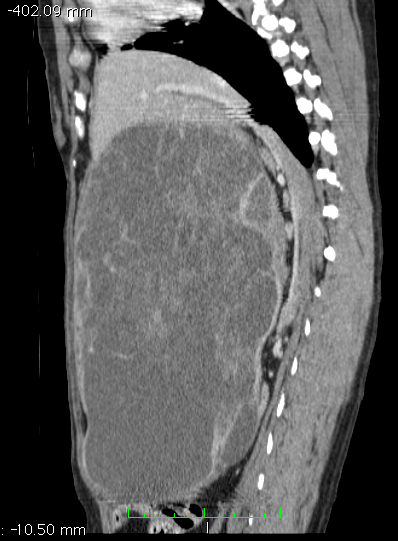

Buster is an 8 year old retriever who started to go off his food. Clinical examination soon identified a very large abdominal mass which was thought to be either hepatic or splenic in origin. Computerised Tomography (CT) was used to assess the organ of origin and to stage the tumour (i.e. assess for any metastasis) and no abnormalities were found other than a nodular, massively enlarged spleen.

Sagital and coronal reconstructed CT images showing a massive splenic mass occupying the majority of the dog’s abdominal cavity